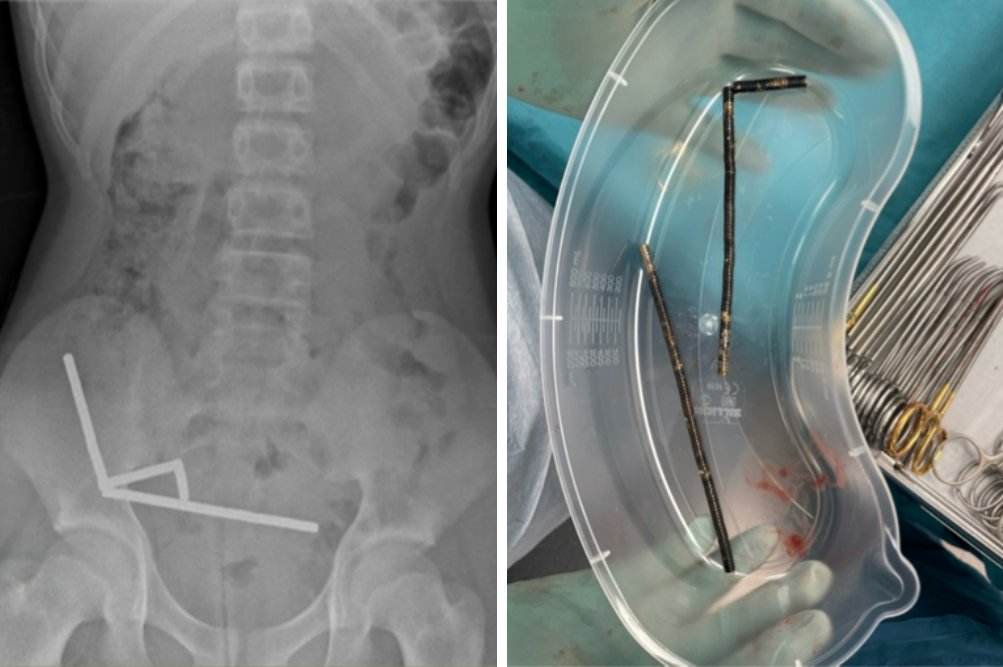

Na levi je rentgenska slika trebuha s štirimi verižnimi nizi magnetov v desnem spodnjem delu trebuha, na desni pa približno 80 do 100 močnih magnetov, odstranjenih med operacijo.

Zdravniki so ugotovili, da so se magneti v njegovih prebavilih spojili in oblikovali štiri verige, kar je povzročilo poškodbe črevesja. Kirurgi so med operacijo odstranili magnete in morali odstraniti tudi dele poškodovanega črevesja.

Prva slika s puščico kaže na dva dela črevesja, zlepljena zaradi magnetov. Druga slika prikazuje krog, ki označuje del slepega črevesa, kjer je zaradi pritiska prišlo do odmrtja tkiva, puščica pa kaže na verigo magnetov v spodnjem delu tankega črevesa.